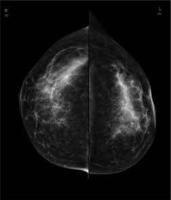

Figure 1

Full-field digital mammography of both breasts in craniocaudal view; no abnormalities are to be seen